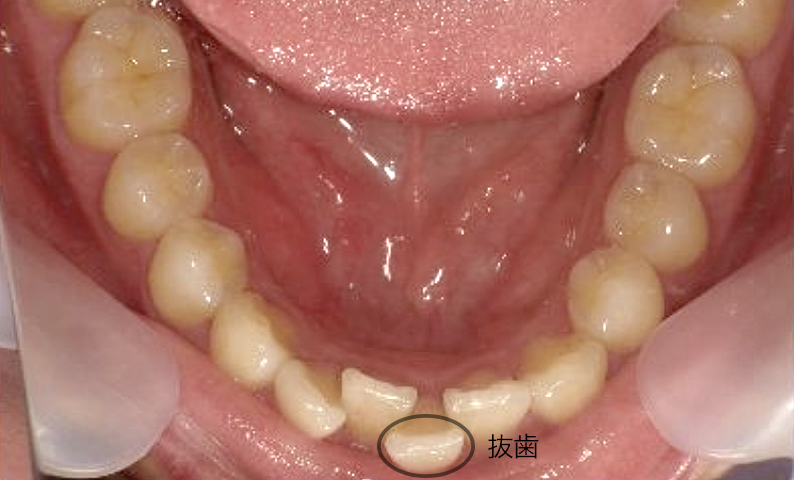

症例_025 上下顎の部分矯正

治療期間:13ヶ月金額:51万円+税女性前歯のガタガタ出っ歯

| Before | After |

|---|---|

|